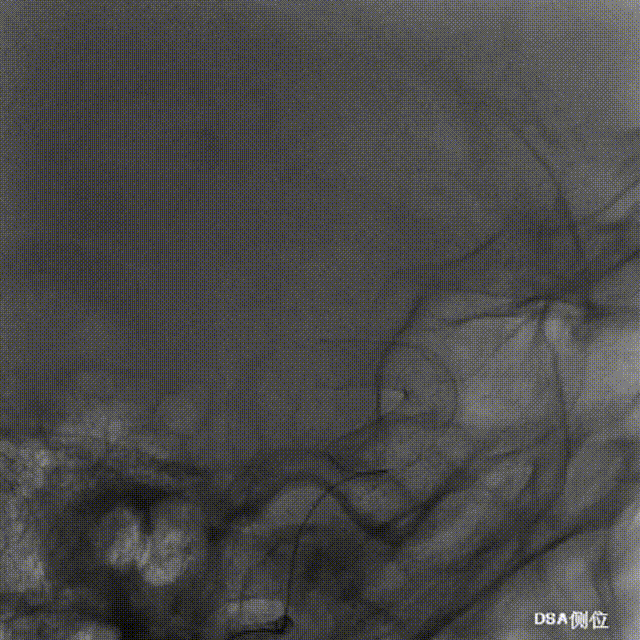

Tubridge Plus Case 1